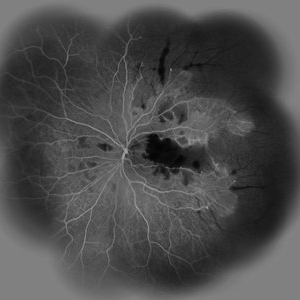

Acute Idiopathic Occlusive Retinal Vasculitis Acute Idiopathic Occlusive Retinal VasculitisMay 31 2014 by Hamid Ahmadieh, MD Wide- field fluorescein angiogram of the left eye of a 28-year-old woman with acute drop of vision due to occlusive retinal vasculitis leading to extensive capillary nonperfusion and macular infarction. Photographer: Naghmeh Nozhat, Negah Eye Center, Tehran Imaging device: Heidelberg Spectralis Condition/keywords: capillary nonperfusion, retinal infarction, retinal vasculitis

Acute Idiopathic Occlusive Retinal Vasculitis Acute Idiopathic Occlusive Retinal VasculitisMay 31 2014 by Hamid Ahmadieh, MD Mid- phase fluorescein angiogram of the left eye of a 28-year-old woman with acute drop of vision due to occlusive retinal vasculitis leading to extensive capillary nonperfusion and macular infarction. Photographer: Naghmeh Nozhat, Negah Eye Center, Tehran Imaging device: Heidelberg Spectralis Condition/keywords: capillary nonperfusion, retinal vasculitis

Acute Idiopathic Occlusive Retinal Vasculitis Acute Idiopathic Occlusive Retinal VasculitisMay 31 2014 by Hamid Ahmadieh, MD Early phase fluorescein angiogram of the left eye of a 28-year-old woman with acute drop of vision due to occlusive retinal vasculitis leading to extensive capillary nonperfusion and macular infarction. Photographer: Naghmeh Nozhat, Negah Eye Center, Tehran Imaging device: Heidelberg Spectralis Condition/keywords: retinal vasculitis

Acute Idiopathic Occlusive Retinal Vasculitis Acute Idiopathic Occlusive Retinal VasculitisMay 31 2014 by Hamid Ahmadieh, MD Fundus autofluorescence image of the left eye of a 28-year-old woman with acute drop of vision due to occlusive retinal vasculitis leading to extensive nerve fiber layer infarction and retinal hemorrhages. Photographer: Naghmeh Nozhat, Negah Eye Center, Tehran Imaging device: Heidelberg Spectralis Condition/keywords: fundus autofluorescence (FAF), retinal vasculitis

Acute Idiopathic Occlusive Retinal Vasculitis Acute Idiopathic Occlusive Retinal VasculitisMay 31 2014 by Hamid Ahmadieh, MD Color fundus photograph of the left eye of a 28-year-old woman with acute drop of vision due to occlusive retinal vasculitis leading to extensive nerve fiber layer infarction and retinal hemorrhages. Photographer: Naghmeh Nozhat, Negah Eye Center, Tehran Condition/keywords: color fundus photograph, cotton wool spots, retinal hemorrhage, retinal ischemia